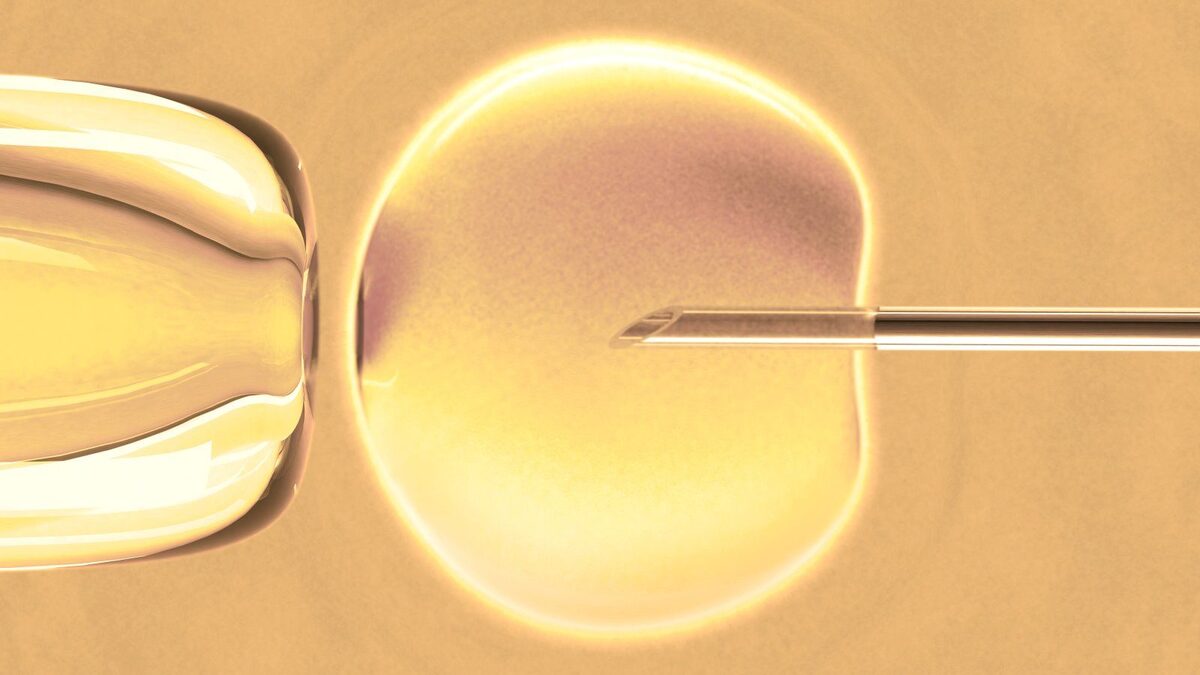

“Butik tedavi” tüp bebekte başarıyı artırıyor Sağlık From Pinterest

“Butik tedavi” tüp bebekte başarıyı artırıyor Sağlık From Pinterest

“Butik tedavi” tüp bebekte başarıyı artırıyor Sağlık